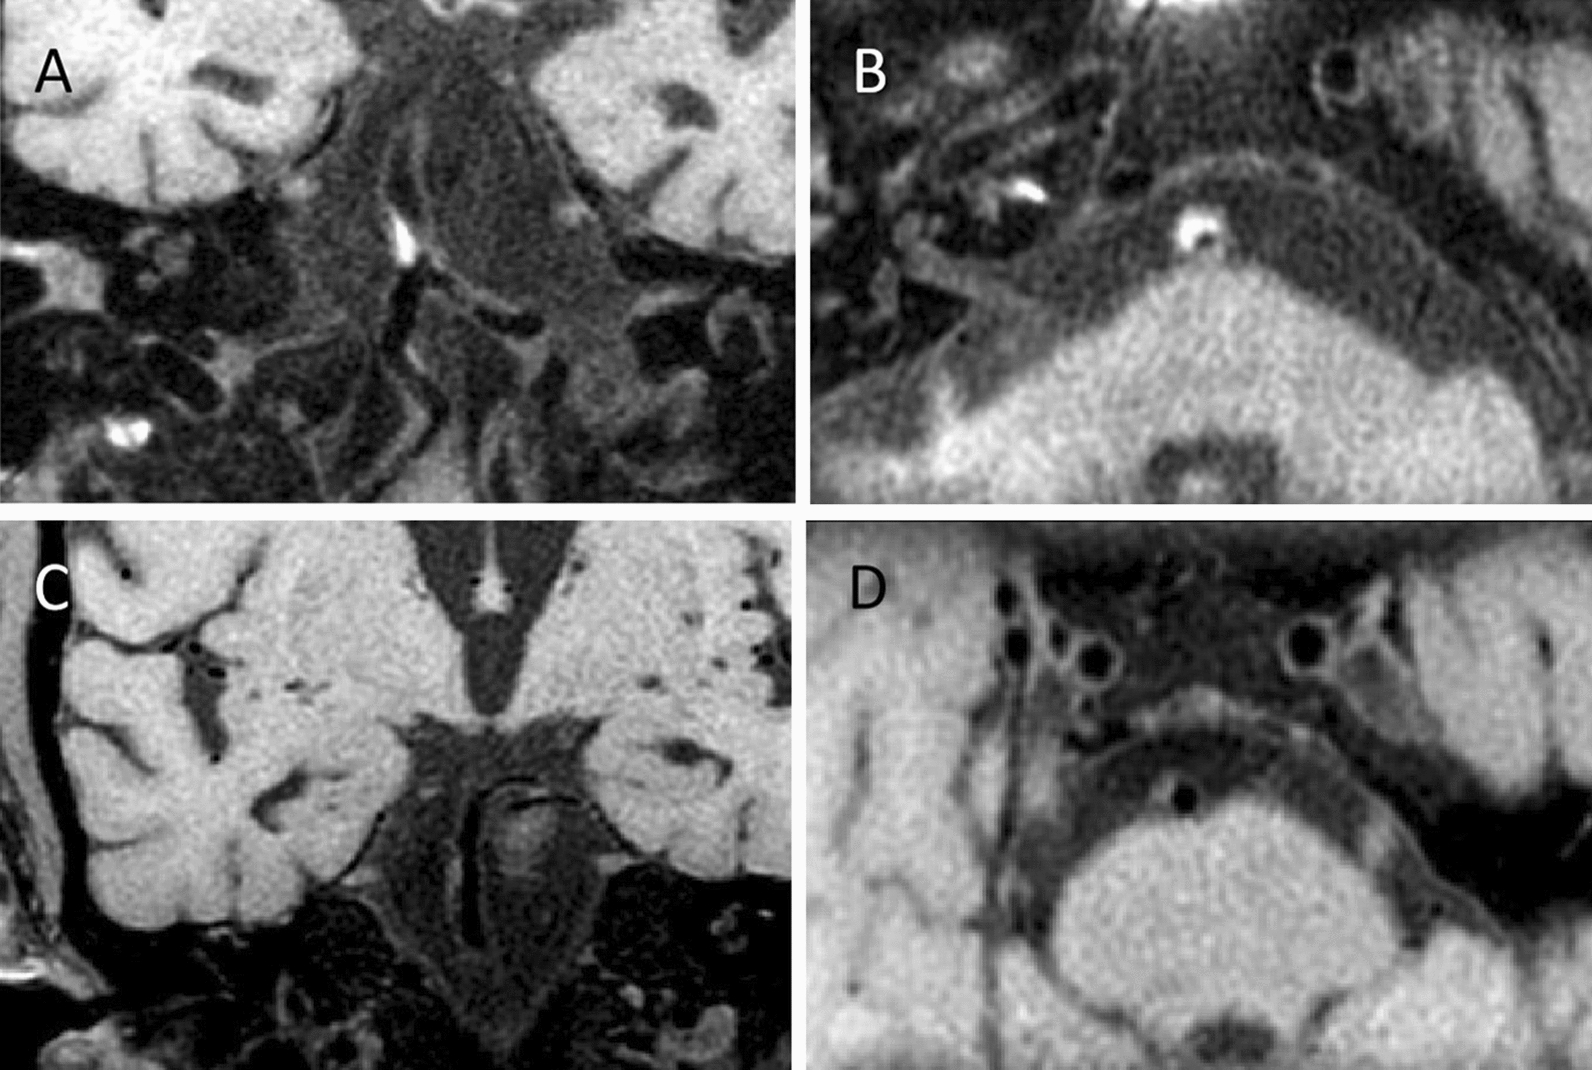

The atherosclerotic plaque was defined as an eccentric wall thickening, whereas the thinnest part was estimated to be < 50% of the thickest part by visual inspection on axial CUBE images [19] (Fig. 1). The presence or absence of BA plaque was identified by two experienced readers (Z.J. and X.Y.) blinded to MRA findings. The differences between the two observers were solved by consensus. To assess intra-observer reproducibility, CBUE images were reevaluated by one reviewer (Z.J.) one month later.

Fig. 1.

Example figures of plaques on 3D CUBE T1WI. An atherosclerotic plaque was present on coronal image (a) and corresponding reconstructed axial image (b) from a 79 years old male patient. Images C and D are from another male patient with 64 years old. An atherosclerotic plaque can be found on coronal image (c) and corresponding reconstructed axial image (d)